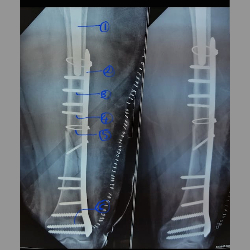

Peri prosthetic fracture

Makes readers familiar with Vancouver classification of peri prosthetic fractures.

Peri prosthetic fracture

Makes readers familiar with Vancouver classification of peri prosthetic fractures.